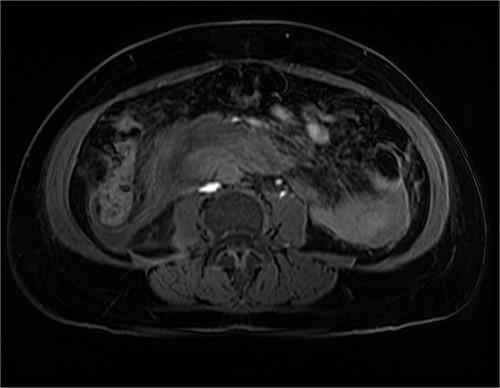

After further discussion with the reporting radiologist, a magnetic resonance imaging (MRI) was performed, which confirmed the presence of an acute periduodenal hematoma surrounding D2 and D3, lying in the retroperitoneal space, anterior to the right perirenal space. Etiology was uncertain. No abnormal enhancement within the bowel to suggest a bowel wall lesion or infiltrating mass (Figs 3 and 4).

MRI abdomen, axial view. T2 hypointense, T1 iso to hyperintense material surrounding D2/D3 without enhancement in keeping with hemorrhage. No vascular or bowel wall lesion identified.